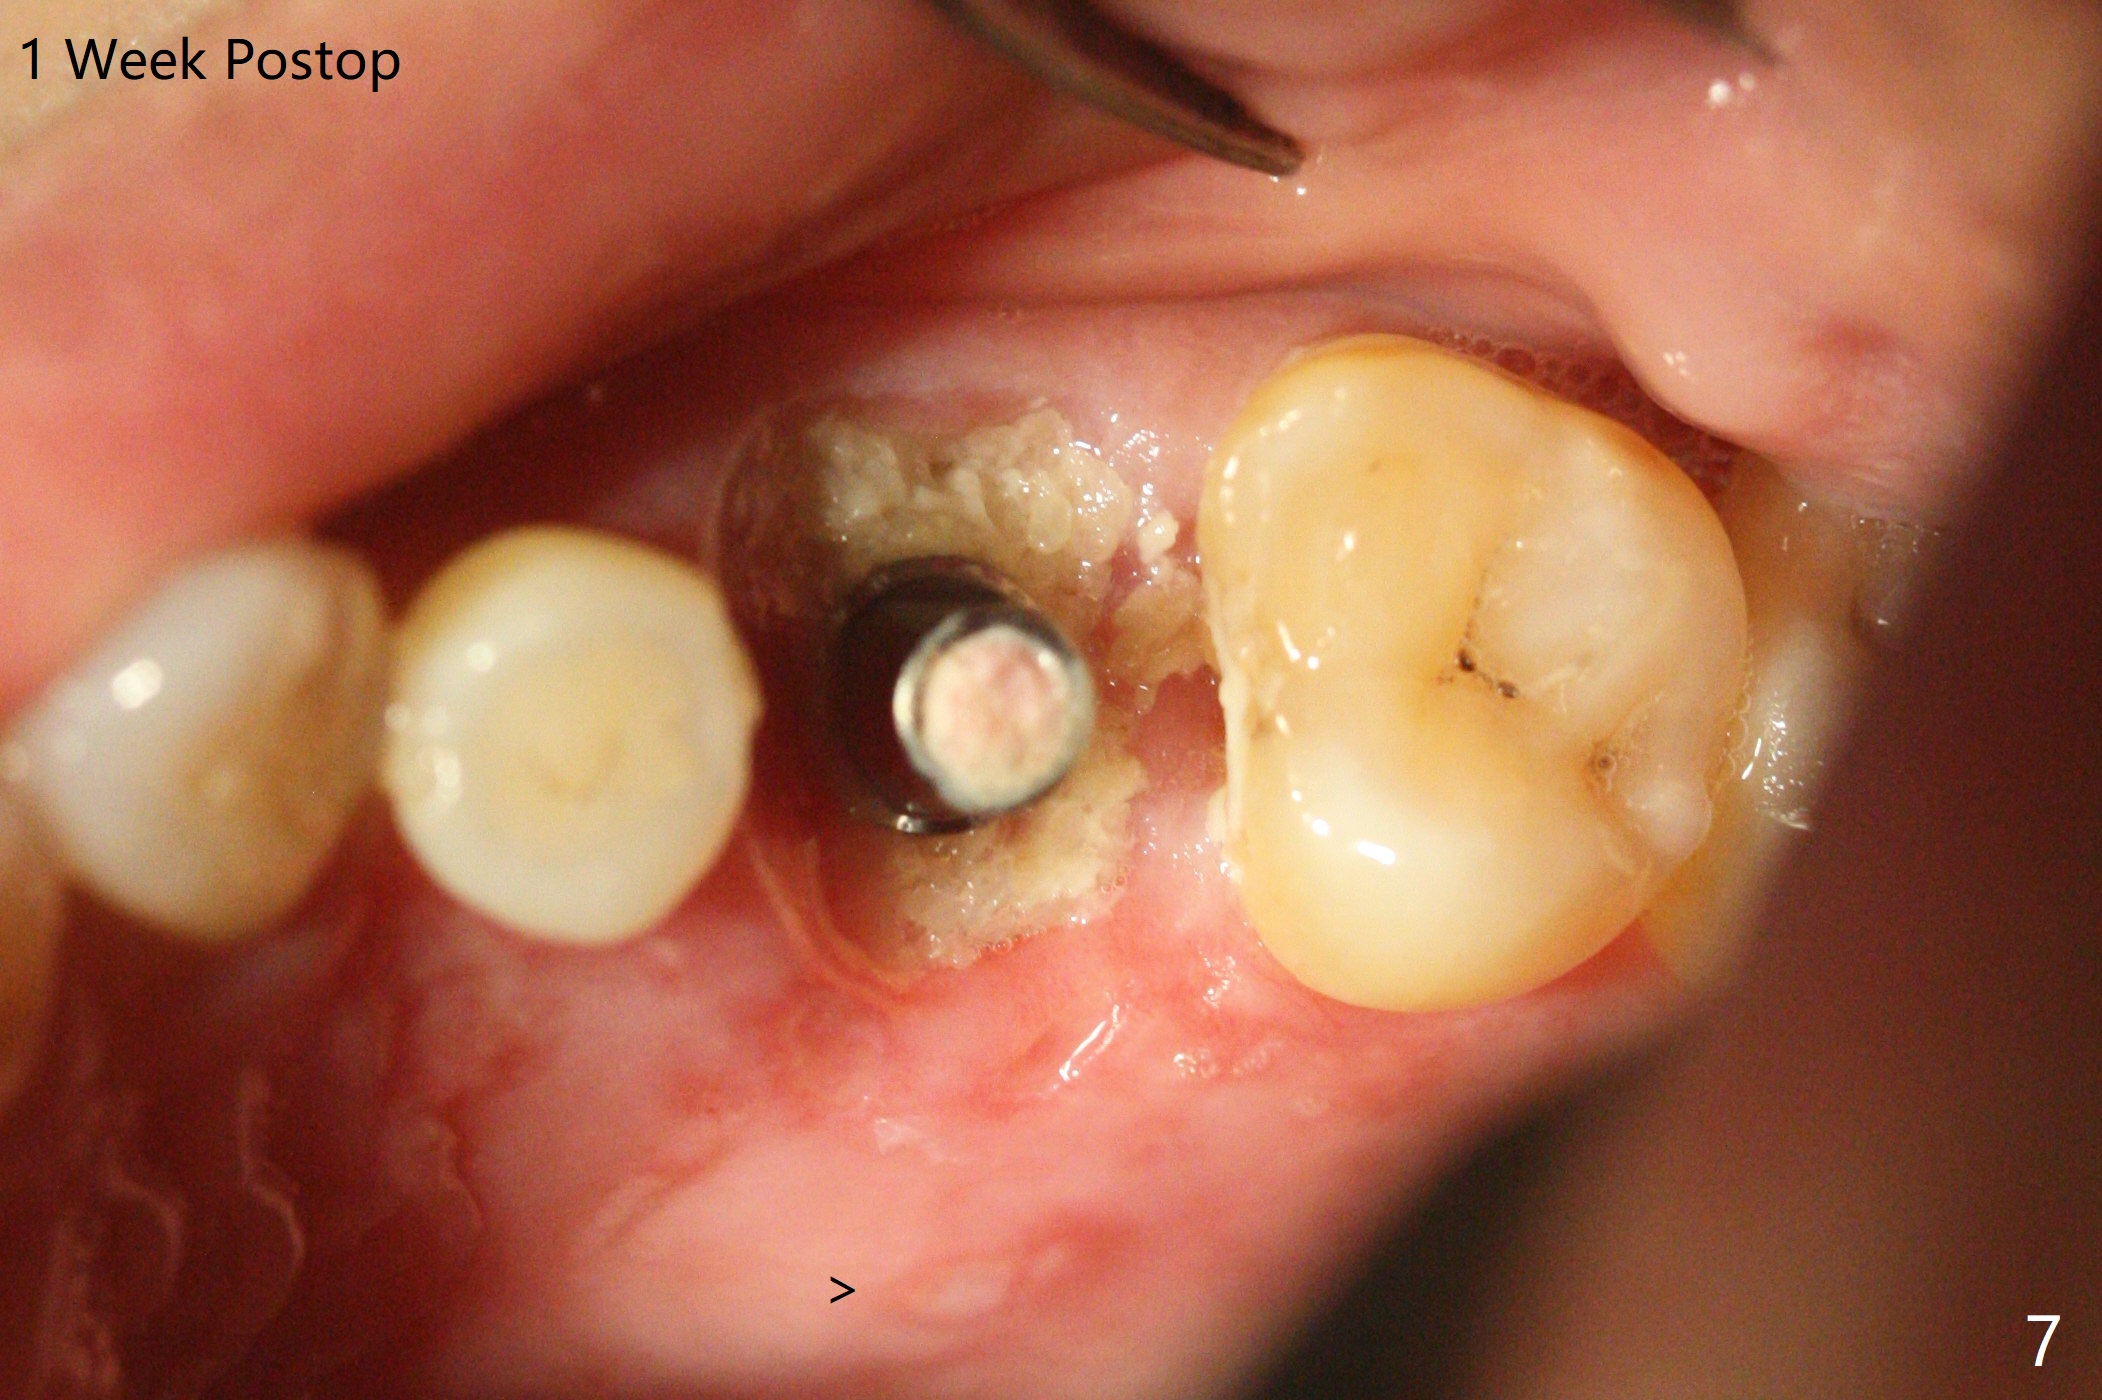

虽然没有保留左上6牙根,但是导板好像帮助钻洞(O)正好位于中隔当中(图一,二)。使用4.5(不是4.0)x10毫米钻头后,粘性骨粉和报废植体完成上颌窦提升术(图三:S)。拔除第一磨牙后发现第二磨牙近中面龋齿,立刻进行保守修补(图三:箭头);两个磨牙之间还有骨质吸收(*)。放置正式植体(10Ncm)后(图四),三个牙槽窝填入骨粉,包括近中颊侧(MB)和远中颊侧(DB),这时磨牙间缺损初步填补(*),然后放置基台以及基台周围骨粉,进一步充填磨牙间缺失(图五:*)。术后临时牙冠脱落两次,病人自己放回去,术后一周取出牙冠,骨粉还在(图六),腭侧有单纯疱疹病变(图七:>),开抗病毒漱口水处方,然后使用临时粘固粉。术后7个月15号牙近中牙槽嵴增高大约1.4毫米(图八:空箭头,从近中最颈部树脂算起)。术后七个月临时牙冠一直使用,防止食物坎塞,有利于骨质再生。术后7个月基台在口内没有更动(术中手拧紧),牙冠口内粘固,少量粘固剂遗留(图八:^)。牙冠/基台取出,去除粘固剂,牙冠/基台就位,用扳手拧紧(30 Ncm),基台与植体仍保持完全接触(图九)。只要植体植入角度好,没有倒凹,牙冠/基台再次就位就没有问题。